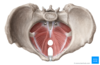

Introduce the uterus

Structure: flattened pear shape organ 8x5x3 made from body and cervix

LOCATION

•Anterior to rectum, posterosuperior to the bladder

FUNCTION

•Site for reception, retention & nutrition of the fertilized ovum

Label the body of the uterus

•Fundus: regionof the uterus above where the uterine tubes enter

•

- Body: flattened in an anterior /posterior direction

- Cornu (‘horns’): where the uterus is joined by the uterine tubes

- Vesical surface (anterior)

- Related to the bladder

- Intervening vesicouterine pouch

- Intestinal surface(posterior)

- Related to coils of small intestine and rectum

- Rectouterine pouch (pouch of Douglas)

- Isthmus

What are the ligaments encompassing the uterus?

Round Ligament

Broad Ligament